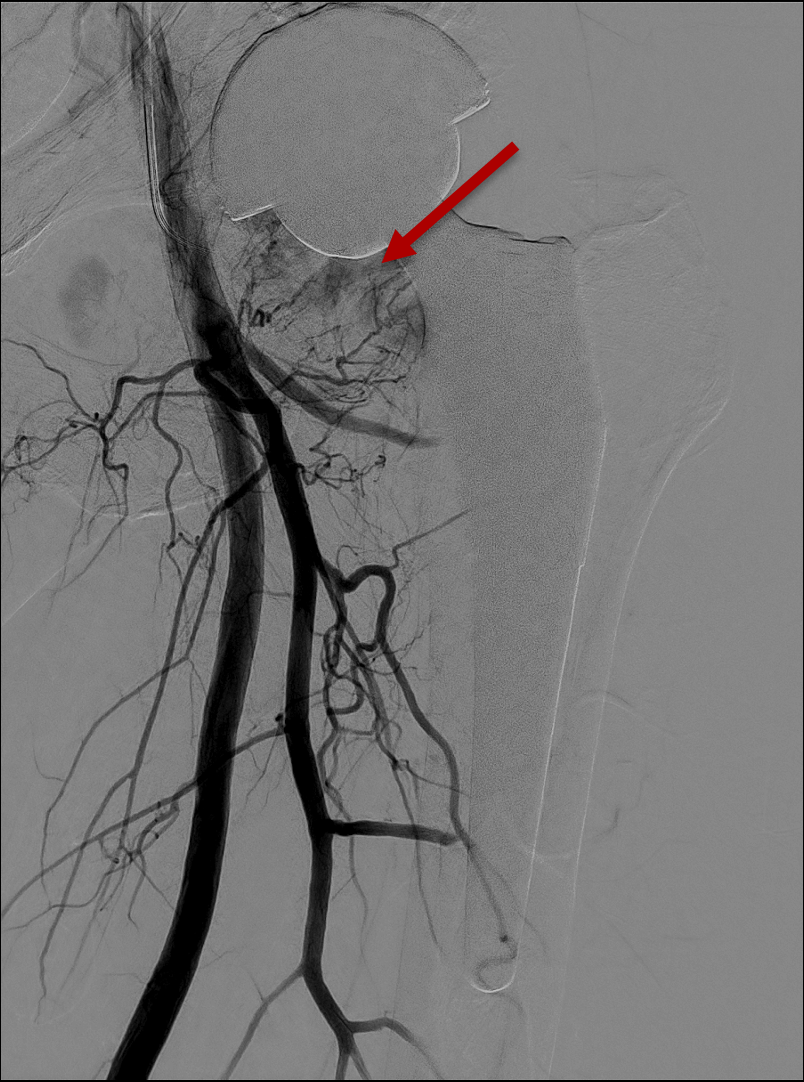

Pre-embolisation angiogram

Marked blush in the medial compartment. Indicating severe chronic inflammation, formation of neo-vessels and neo-nerves.

Post-embolisation angiogram

Complete pruning of the abnormal blush. Preservation of the main vessel stems.